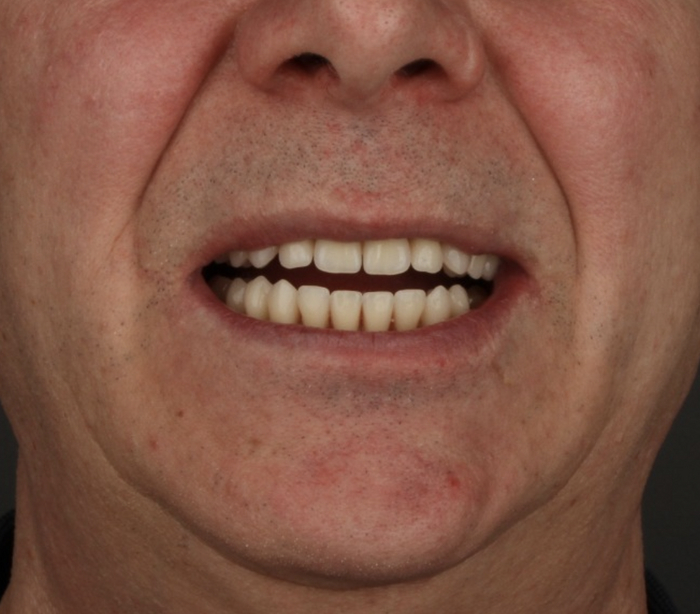

Хорошо выглядят и блестят, по фото с телефона мало что понятно, но в полости рта они смотрятся гораздо интересней.

Нижний протез плотно, даже с небольшим давлением, прилегает. Верхний через пару месяцев будем делать такой-же.

Ну и лучшая награда для меня — улыбка пациента!